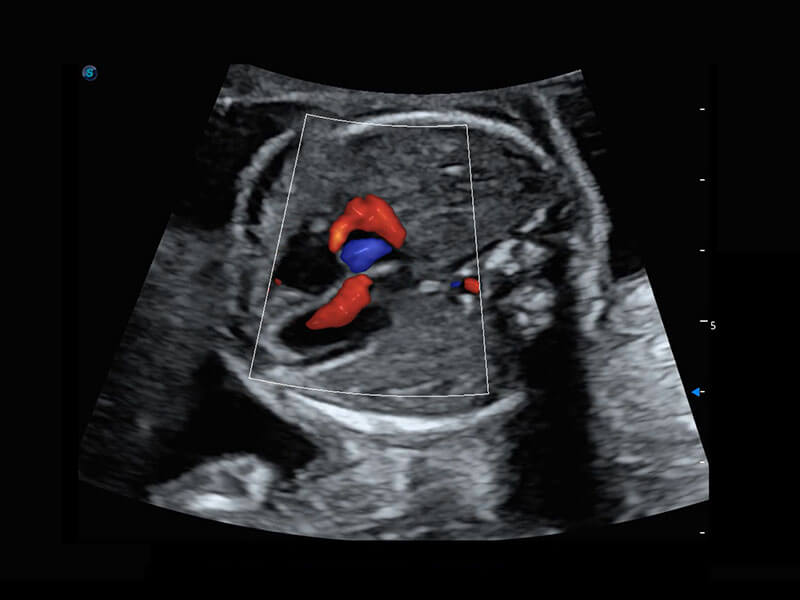

P60搭载一系列胎儿心脏成像技术,实现精细的胎儿心脏评估。

四腔心血流

右室双出口